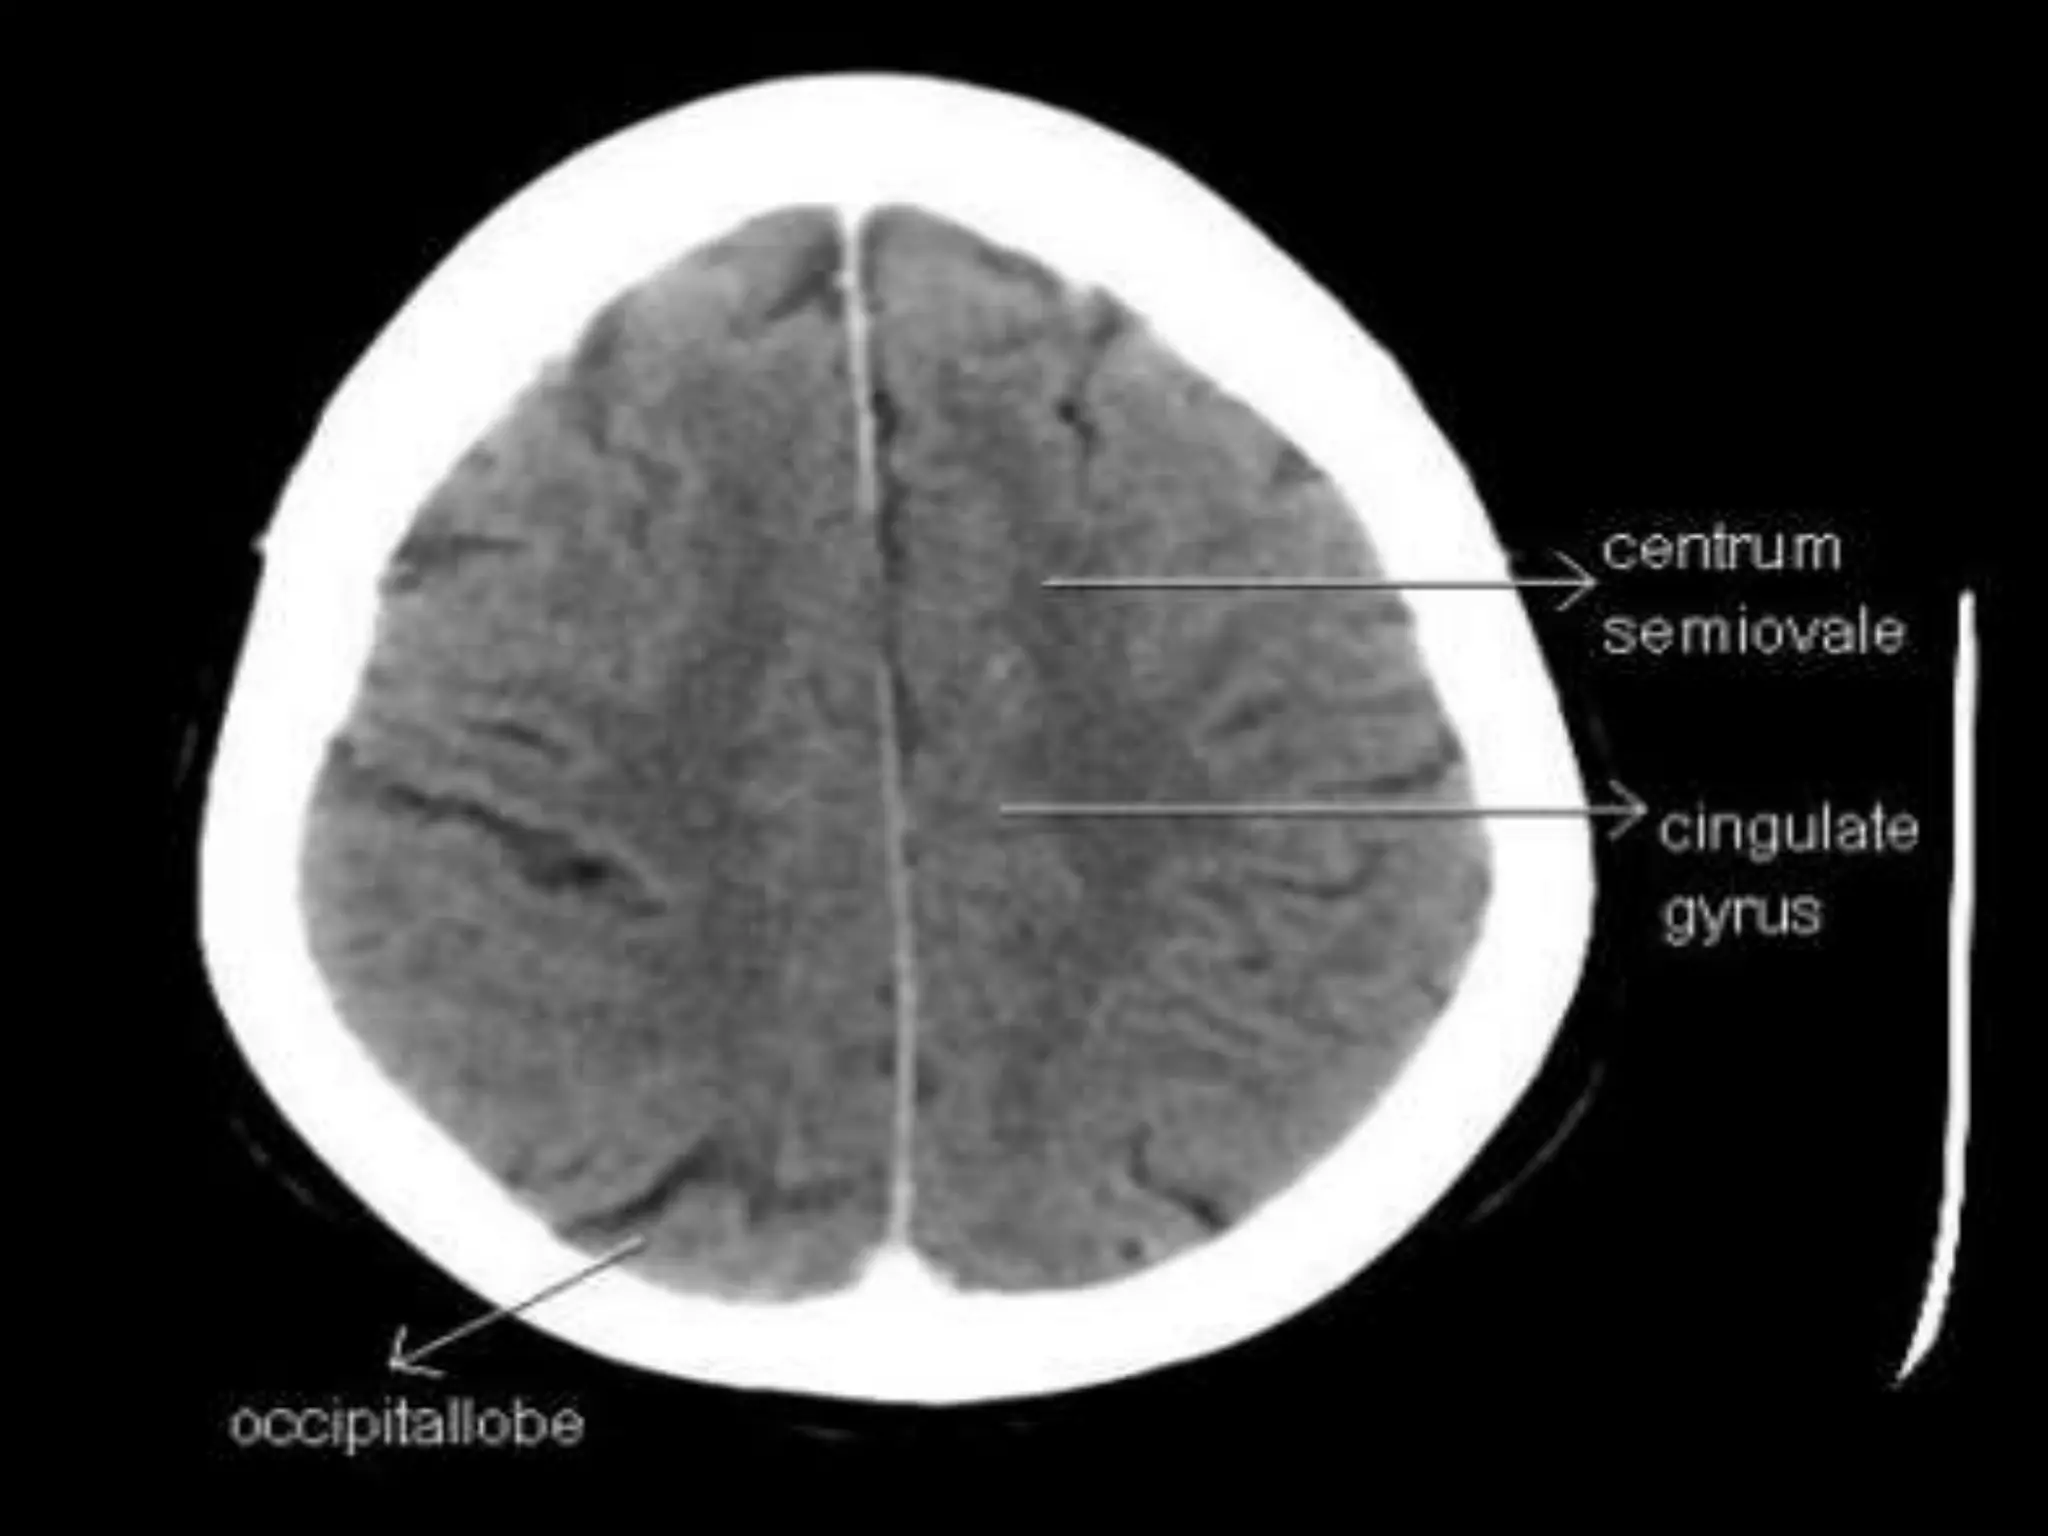

Axial CT Anatomy.

Sectional Anatomy: NormalAxial CT and MRI Anatomy. On CT and MR scans, the brain has been briefly viewed in infratentorial and supratentorial sections, as described below. CT scans are performed with a 15- to 20-degree angulation to the canthomeatal line at 8-mm increments. MRI scans are generally obtained parallel to the AC-PC line in the axial plane with 6-mm slice thickness. Using the sagittal view, the coronal sections are acquired parallel to the brain stem, and the sagittal sections are obtained perpendicular to the axial section. On MRI studies, cranial nerves IX and X can be demonstrated at this level because they emerge from the postolivary sulcus. The posterior aspect of the cerebellar hemispheres is outlined by the inferior portion of the cisterna magna.